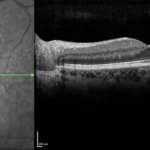

Figura 4. Bscan eseguita sulla lesione.